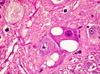

MDx?

Nodular adrenocortical hyperplasia

senile change